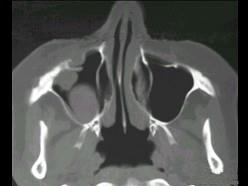

女性,50岁,右鼻塞、脓涕3个月,CT、MRI检查如图所示,请选择正确的答案 ( )

• A.右侧上颌窦积液

• B.右侧上颌窦腺样囊性癌

• C.右侧上颌窦粘膜下囊肿

• D.右侧上颌窦黏液腺瘤

• E.右侧上颌窦黏液囊肿

答案: B